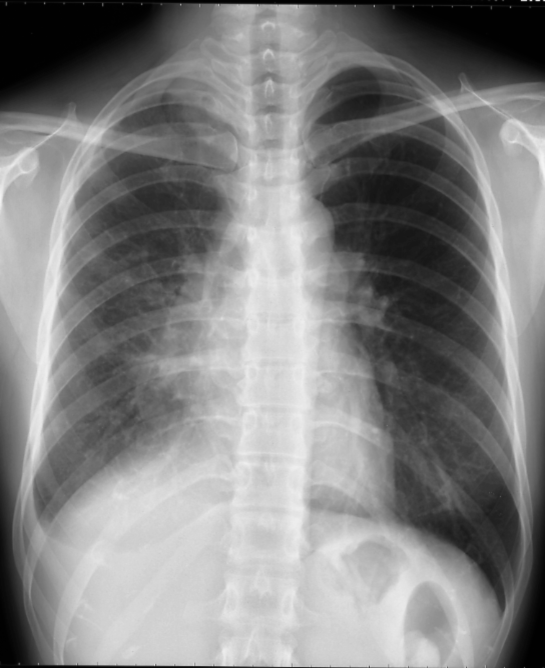

右上葉の無気肺の胸部単純X線写真

胸部正面写真で傍気管線が消失し、縦隔上部のシルエットが消失し(シルエットサイン陽性)、気管が右側に偏位している。